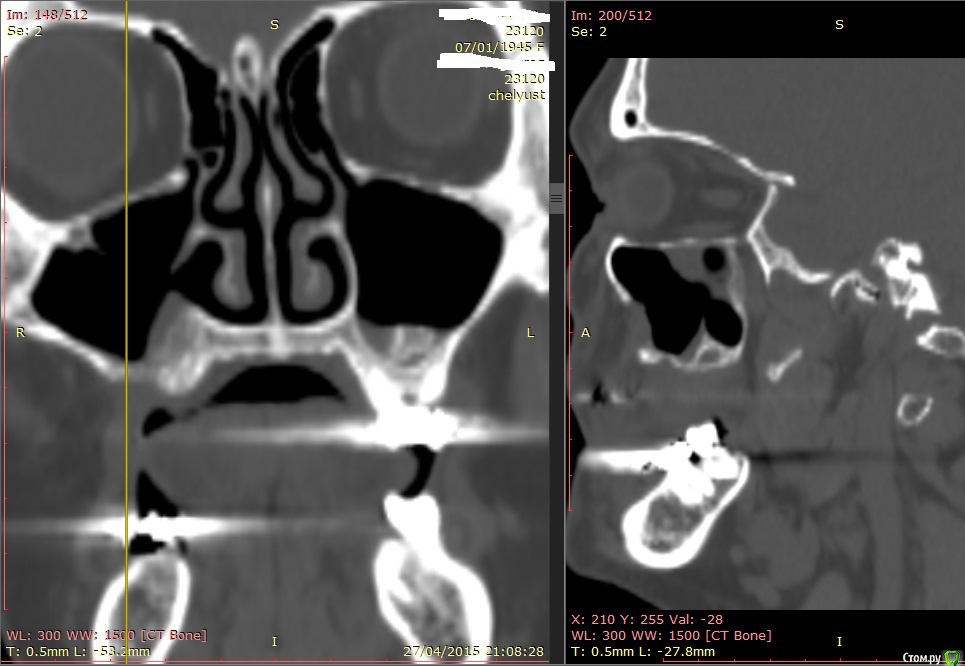

Alexey Doc Опубликовано 29 апреля, 2015 Поделиться Опубликовано 29 апреля, 2015 В клинику с целью протезирования обратилась пациентка 70 лет.Ортопед направил на консультацию. В анамнезе: со слов больной год назад удален зуб 1.6 после чего сформировался оро-антральный свищ. В январе 2015 года выполнена правосторонняя радикальная гайморотомия с удалением 1.5, 1.7 зубов. Сопутствующая патология в стадии компенсации.На сегоднещний день жалоб кроме отсутствия зубов нет.В полости рта : верхний свод преддверия справа плавно перетекает в небо мощным тяжем подвижной слизистой шириной примерно 15-17 мм . Альвеолярный отросток отсутствует. Какой\ие минимально инвазивные( учитывая возраст пациентки) способы аугментации вы бы применили у этой больной для последующего протезирования с опорой на имплантатах? Буду рад любому мнению и рац.предложению.Ниже свежие срезы КТ. Ссылка на комментарий

Alexey Doc Опубликовано 30 апреля, 2015 Автор Поделиться Опубликовано 30 апреля, 2015 ткните пальцем не вижу что то)Хорошо проходимая решетчатая воронка Ссылка на комментарий